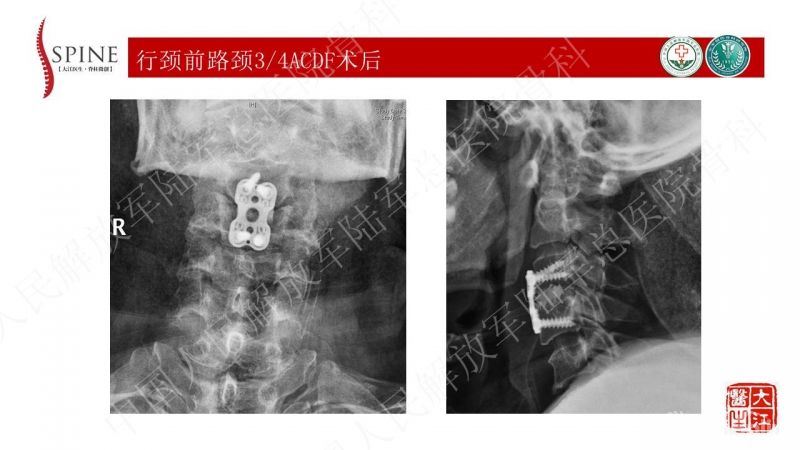

3月前骑车被汽车撞倒,额面部着地,伤后出现双上肢剧烈疼痛,双上肢肌力减弱,以手内肌为主,活动受限,诊为“急性中央型颈脊髓损伤”,后全麻下行“颈前路颈3/4椎间盘切除椎间植骨融合术” 术后患者双上肢症状恢复良好,出院后离床活动即感腰痛剧烈,行走约100米感双下肢疼痛,疼痛主要位于双侧小腿后方,右侧为著,休息后可缓解,但体位改变疼痛加重